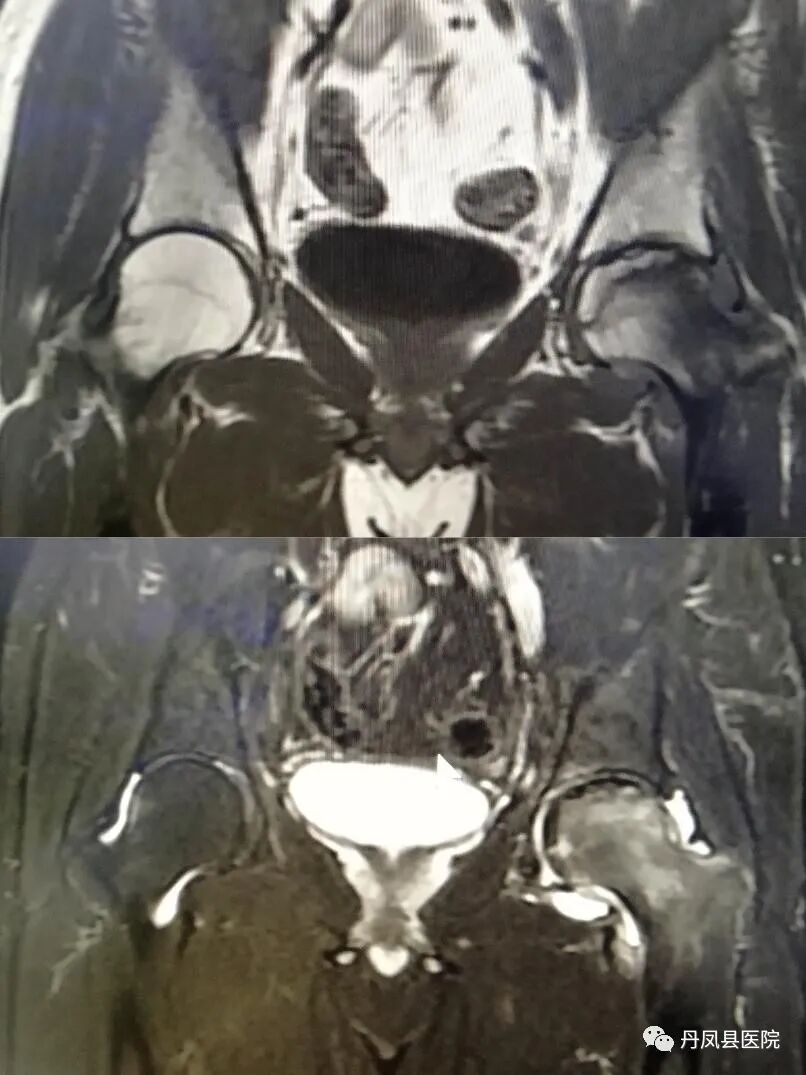

![股骨头缺血坏死.jpg]()

股骨头缺血坏死

优秀的关节成像,清晰显示细微解剖结构、骨骼、关节软骨、韧带等结构。